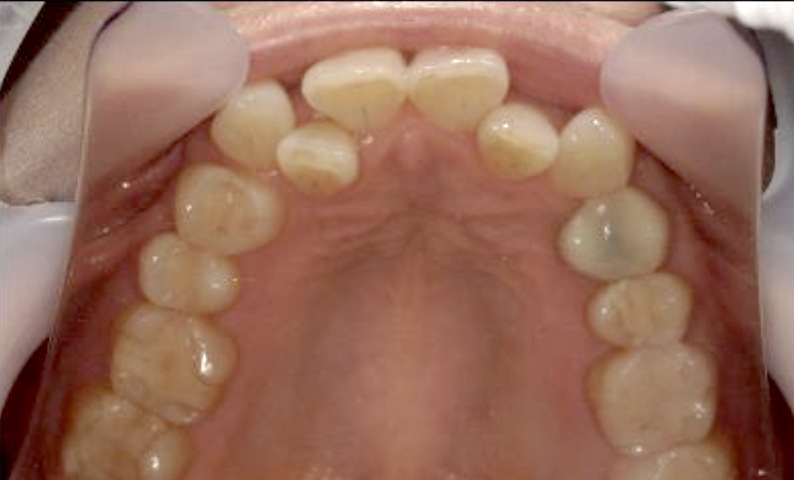

症例_003 下顎だけの部分矯正

治療期間:10ヶ月金額:24万円+税女性前歯のガタガタ下の前歯だけ上顎は補綴治療中

| Before | After |

|---|---|

|